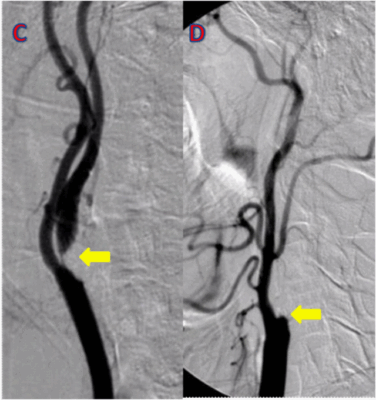

Bu testler sonucunda tedavi gerektirebilecek kritik bir darlık saptanırsa veya tanı hala belirsizse, “altın standart” olarak kabul edilen kateter anjiyografisine başvurulur. Bu işlemde, genellikle el bileği veya kasıktaki atardamardan ince bir tüp (kateter) ile girilerek, kalbi veya diğer organları besleyen damarların içine kadar ulaşılır. Buradan verilen özel bir boya madde sayesinde, damarların röntgen filmi çekilir ve tıkanıklıklar net bir şekilde görüntülenir. Anjiyografinin en büyük avantajı, teşhisle aynı anda tedaviye (balon/stent) imkan tanımasıdır.